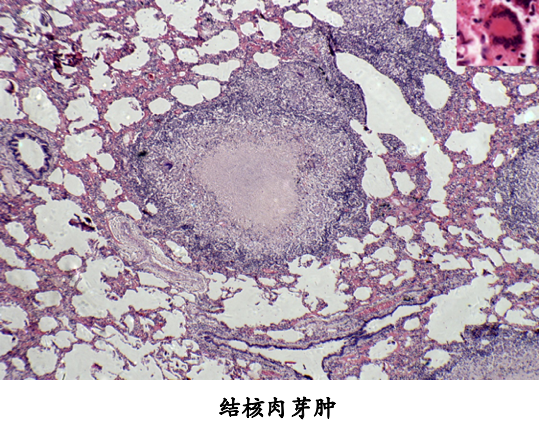

当细菌量少,毒力较低或人体免疫反应较强时,则发生以增生为主的变化,形成具有诊断价值的结核结节,结核结节(tubercle)是在细胞免疫的基础上形成的,由上皮样细胞(epithelioid cell),朗汉斯(Langhans)巨细胞加上外周局部集聚的淋巴细胞和少量反应性增生的纤维母细胞构成:

干酪样坏死典型者结节中央有干酪样坏死(*)

单个结核结节非常小,直径约0.1mm,肉眼和X线片不易看见。三、四个结节融合成较大结节时才能见到。这种融合结节境界分明,约粟粒大小,呈灰白半透明状。有干酪样坏死时略显微黄,可微隆起于器官表面。

1、急性全身粟粒性结核病 结核杆菌在短时间内一次或反复多次大量侵入肺静脉分支,经左心至大循环,播散到全身各器官如肺、肝、脾和脑膜等处,可引起急性全身性粟粒性结核病(acute systemic miliary tuberculosis)。肉眼观,各器官内均匀密布大小一致,灰白色,圆形,境界清楚的小结节。镜检,主要为增生性病变,偶尔出现渗出,坏死为主的病变。多见于原发性肺结核病恶化进展,又可见于其他类型的结核病播散,甚至见于死产的胎儿。临床上病情凶险,有高热衰竭、烦燥不安等中毒症状。X线可发现两肺有散在分布、密度均匀,粟粒大小细点状阴影,病情危重,若能及时治疗,预后仍属良好。少数病例可因结核性脑膜炎而死亡。

3、急性肺粟粒性结核病 由于肺门、纵隔、支气管旁的淋巴结干酪样坏死破入邻近大静脉,或因含有结核杆菌的淋巴液由胸导管回流,经静脉入右心,沿肺动脉播散于两肺,而引起两肺急性粟粒性结核病。当然急性粟粒性肺结核也可是急性全身性粟粒性结核病的一部分。肉眼观,肺表面和切面可见灰黄或灰白色粟粒大小结节。

4、慢性肺粟粒性结核病 多见于成年人。患者原发灶已痊愈,由肺外某器官的结核病灶内的结核杆菌间歇入血而致病。病程较长,病变新旧、大小不一。小的如粟粒,大者直径可达数cm以上。病变以增生性改变为主。